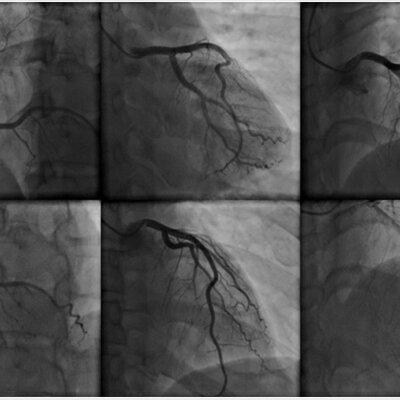

ANGIOGRAFIA

Timeline: ANGIOGRAFIA